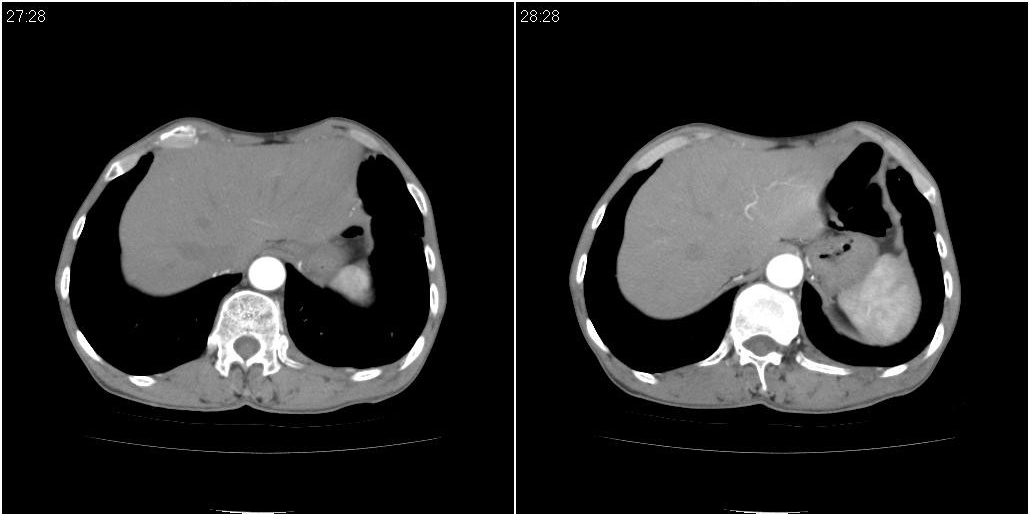

标题: CT25416:男性,70岁。胸片发现右下肺斑片状阴影

以下是ct检查的情况:

标题: ct增强:

1)右肺中叶慢性炎症并支气管扩张,节段性肺不张。2)两肺下叶支气管扩张。

考虑右肺中叶感染。左肺下叶支扩。